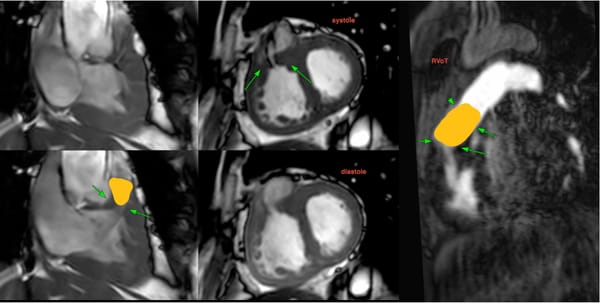

HCM with LVOT obstruction

COD 158 - Septum Predominant HCM and RVoTo

RVoTo involvement in HCM is uncommon but diagnosing it may change the management plan and prognosis